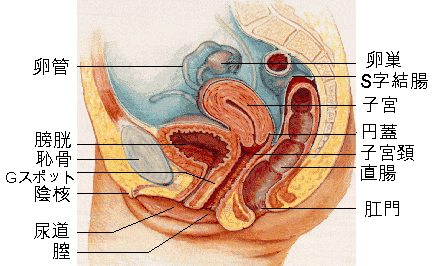

女性器の断面図 Listen さくやの囁き

子宮横からの断面図 名称付き メディカルイラスト図鑑 無料の医療 美容素材集

骨盤 女性 解剖学 切断断面 卵巣 卵管 子宮 膀胱 膀胱 尿路 クリトリス 尿道 尿道括約筋 膣 外陰結腸 直腸括約筋が示される のイラスト素材